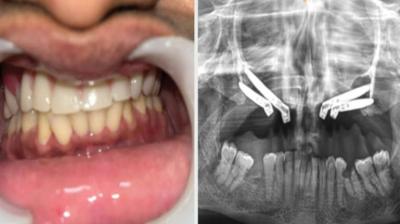

एम्स भोपाल डेंटल टीम ने लिखा इतिहास, इंटरनेशनल जर्नल में केस भेजा

6 Sep, 2025 10:00 PM IST | JANSEWASAMACHAR.COM

एम्म में जटिल सर्जरी को सफलतापूर्वक अंजाम दिया है। इस सर्जरी में ट्यूमर के कारण काटे गए निचले जबड़े को पैर की हड्डी से दोबारा बनाया गया और उसमें 13...